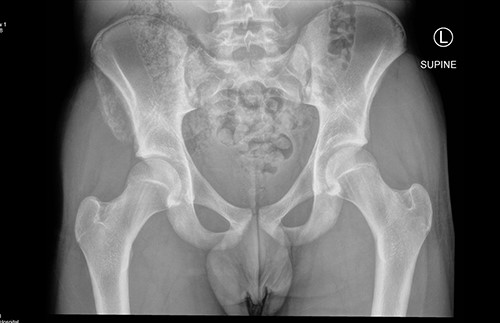

The anterior–posterior plain film X-Ray of pelvis demonstrated an avulsion fracture of the right ASIS and IC apophysis with 1.5 cm displacement (Fig. 1). Lateral view of the hip showed no extension into the joint. There was no radiological evidence of chronic overuse or previous injury. Computed tomography (CT) imaging was performed to better identify the injury; 3D volume reconstruction clearly demonstrated the unique fracture pattern of an ASIS avulsion in addition to an avulsion of the distal iliac apophysis extending ~5 cm with the described displacement (Figs 2–4).

AP radiograph following injury, demonstrating a large avulsion from the right hemipelvis, including the ASIS and portion of the IC apophysis (R - Right).